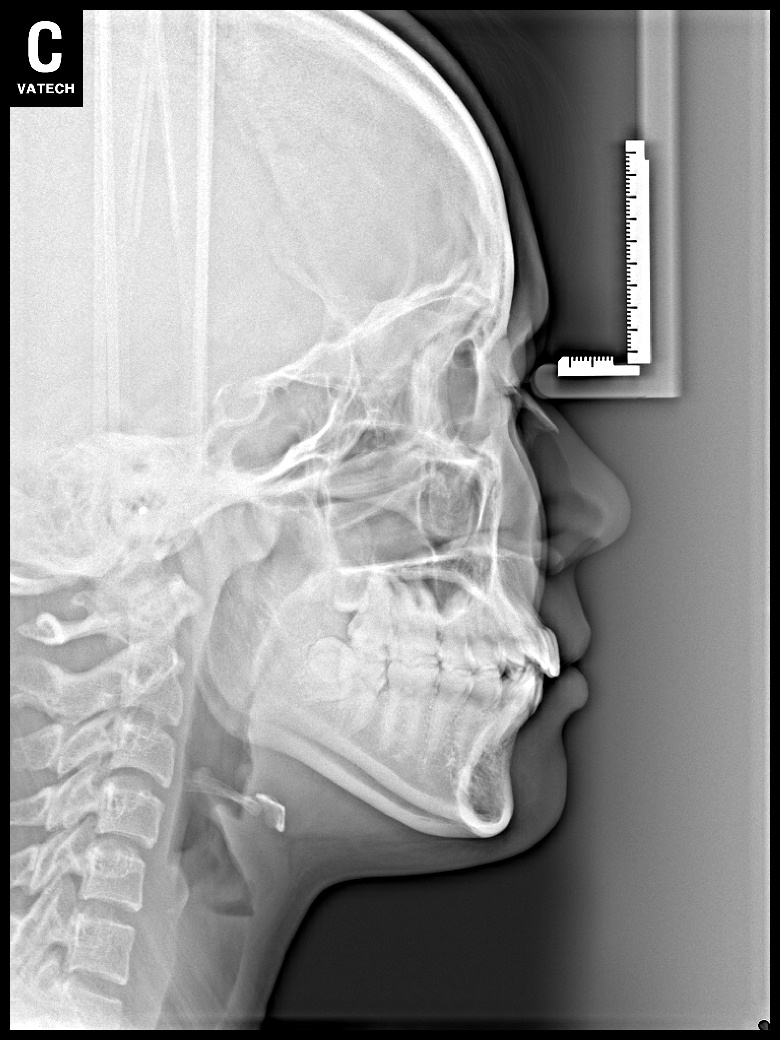

치료 후 사진입니다.